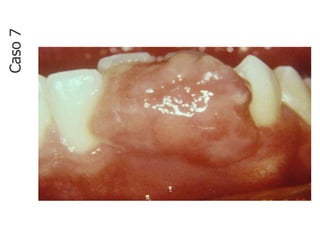

Caso

7

• Lesão fundamental: nódulo

• Localização: mucosa gengival inferior

• Quantidade: única

• Tamanho: 2,0 cm x 1,0 cm

• Borda: bem delimitada

• Cor: rósea com áreas

• avermelhadas

• Base: Pediculada

• Aspecto superficial: lobulado

• Em mucosa gengival inferior, nota-se nódulo

vegetante, de base pediculada, superfície lobulada,

única, coloração rosa claro com áreas avermelhadas e

que mede aproximadamente 2,0 x 1,0 cm em seus

maiores diâmtros.

CASO 7 - Descrição